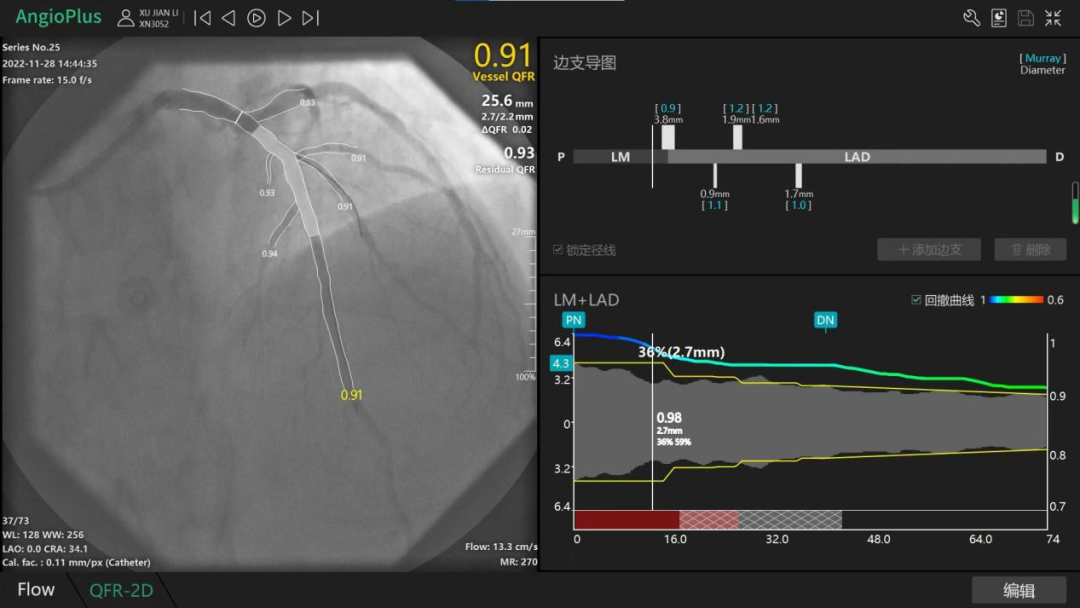

随后,在QRF新技术的指导下,精确预设支架位置、尺寸,心病科介入团队为患者在前降支植入支架1枚,对角支植入药物球囊1枚,术后复查QRF值均提升为0.91。目前患者恢复良好,已无明显的胸闷胸痛症状。